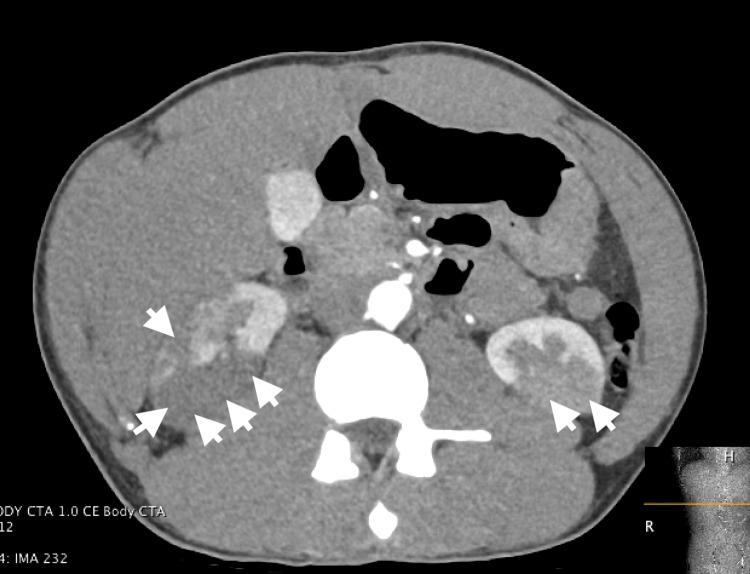

A man in his late 20s presented to the emergency department with sudden-onset abdominal pain. Urinalysis was significant for hematuria and slightly elevated creatinine. A computed tomography (CT) scan with IV contrast revealed bilateral renal infarcts, which was corroborated by a computed tomography angiogram (CTA). Further evaluation by an autoimmune panel demonstrated a positive antinuclear antibody, while echocardiography showed left ventricular non-compaction cardiomyopathy. The workup included consultations with multiple specialities and additional investigations to assess hypercoagulability, vasculitis, and infectious etiologies. Following supportive care, the patient was discharged in stable condition with a plan for outpatient follow-up and further workup, including screening of first-degree family members for left ventricular non-compaction and associated cardiovascular risks. Here we describe a report of a rare case of bilateral renal infarct of possible thromboembolic etiology due to an underlying rare genetic cardiovascular condition.

一名28岁左右的男性因突发腹痛被送往急诊科。尿液分析显示有血尿且肌酐略有升高。静脉注射造影剂的计算机断层扫描(CT)显示双侧肾梗死,计算机断层血管造影(CTA)证实了这一结果。自身免疫检查进一步评估显示抗核抗体呈阳性,而超声心动图显示左心室心肌致密化不全。检查包括与多个专科会诊以及进行额外检查以评估高凝状态、血管炎和感染病因。经过支持治疗,患者病情稳定出院,计划进行门诊随访和进一步检查,包括对一级家庭成员进行左心室心肌致密化不全及相关心血管风险的筛查。在此,我们报告一例罕见病例,其双侧肾梗死可能由潜在的罕见遗传性心血管疾病导致血栓栓塞病因引起。